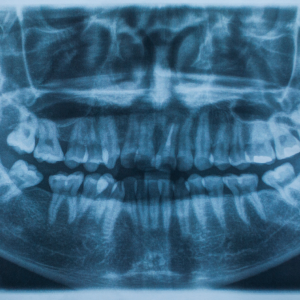

Dental X-rays, a cornerstone service at Malhar Dental Clinic, provide a clear view of what’s happening beneath the gums – a view that is impossible to achieve through regular check-ups. The clinic’s state-of-the-art technology ensures precision and clarity, helping diagnose issues that are invisible to the naked eye.

When Anjali visited Malhar Dental Clinic, she was greeted with warmth and understanding. The clinic’s team, led by Dr. Ravi Kumar, a renowned dentist with over a decade of experience, assured her that they would get to the root of her problem. With a simple, non-invasive procedure, they took a series of dental X-rays that revealed the issue – a hidden cavity nestled between two molars.

Moreover, dental X-rays at Malhar Dental Clinic are not just about addressing pain. They play a crucial role in preventive care, helping detect potential issues before they escalate into serious problems. Regular X-rays can identify early signs of tooth decay, gum disease, and even bone infections, allowing for timely intervention and saving patients from future discomfort and expense.